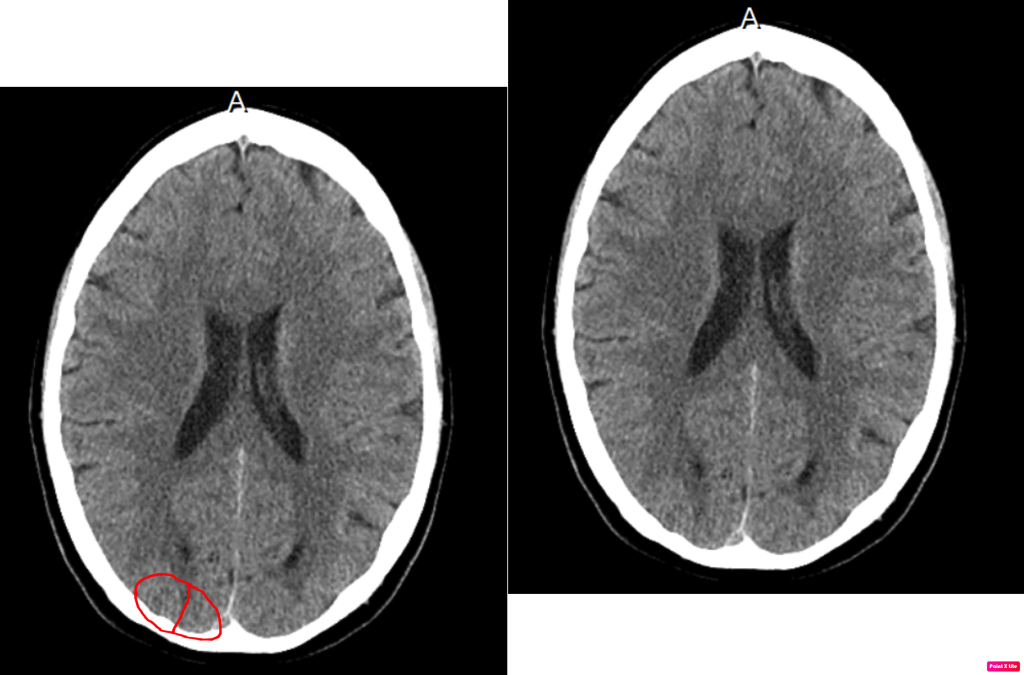

In this scan we can see two little Hamer Focus’ in the occipital lobe. These two hit when I experienced an excessive fear of dying during one of my belching episodes in the middle of the night. Lately, I have been having these more frequently. It feels like air gets stuck in my esophagus and pushes against my heart and lungs which causes a sudden rapid heart rate of up to 150 beats/min at rest. This continues until air gets finally released. During this time my body is under severe stress. Up until recently this scared me to death, because I didn’t know what was happening, and I was scared that my husband wouldn’t find me until it was too late since it was the middle of the night. This fear crept up on me whenever my heart rate would change.

As far as I can tell, these symptoms are lingering chronically since I have experienced this fear quite often as of late. You can see the target like shape of them, but they look like they have slight edema.

The body part that relates to this is my left eye, or more specific the retina. The conflict is the sensation of “fear creeping up my neck”. Once the Hamer Focus appears, the eyesight begins to temporarily deteriorate. The biological meaning of this is the temporary, partial suppression of the retina to “make the fear invisible”.

During the healing phase, the Hamer Focus develops edema, and so does the retina, and separates from the sclera. This can lead to severely deteriorating eyesight which will go back to normal later in the healing phase. If the same conflict hits the same spot over and over again, called recurrence, I can become far-sighted, which I have slowly developed over the last few years.